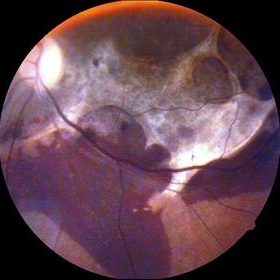

Rerinal Detachment with PVR

Sep 10 2014 by Mehul A Shah

A myopic male patient 35-years-old presented to outdoor and found to have retinal detachment with multiple fixed folds.

Photographer: Drashti Netralaya,Dahod

Imaging device: FF 450

Condition/keywords: proliferative vitreoretinopathy (PVR)